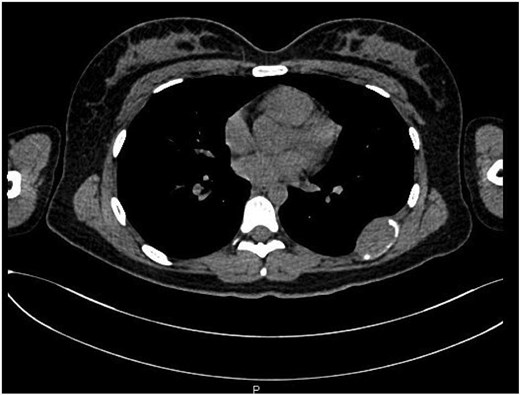

A 21-year-old female presented with a 5-month history of mild pain in the left hemithorax and paravertebral region. She was initially treated with nonsteroidal anti-inflammatory drugs without improvement. A chest X-ray (CXR) revealed a mass involving the seventh rib, leading to her referral to a tertiary care center. A computed tomography (CT) scan confirmed a tumor originating from the left seventh rib, measuring 21 mm × 38 mm (Fig. 1).